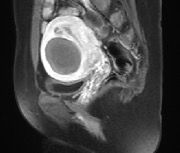

Imaging Outcomes

Figure 4. (A-D). Contrast-enhanced MRI obtained from a 35-year old patient with uterine fibroid. (A). Pre-HIFU MRI showed a significant enhancement of a uterine fibroid located at the anterior wall of the uterus, and the size of the fibroid was 5.6 cm x 4.6 cm x 4.9 cm; (B).1-day post-HIFU MRI showed no enhancement of the treated fibroid, the uterine fibroid was completely ablated; (C). 4-month post HIFU MRI showed the size of the treated fibroid reduced to 5.0 cm x 4.3 cm x 4.2cm, the shrinkage was 28.5%; (D). 10-month post-HIFU MRI showed the size of the treated fibroid reduced to 3.5 cm x 3.0 cm x 3.2cm, and the shrinkage was 73.4% compared to baseline. Images courtesy Prof. Zhang Lien.